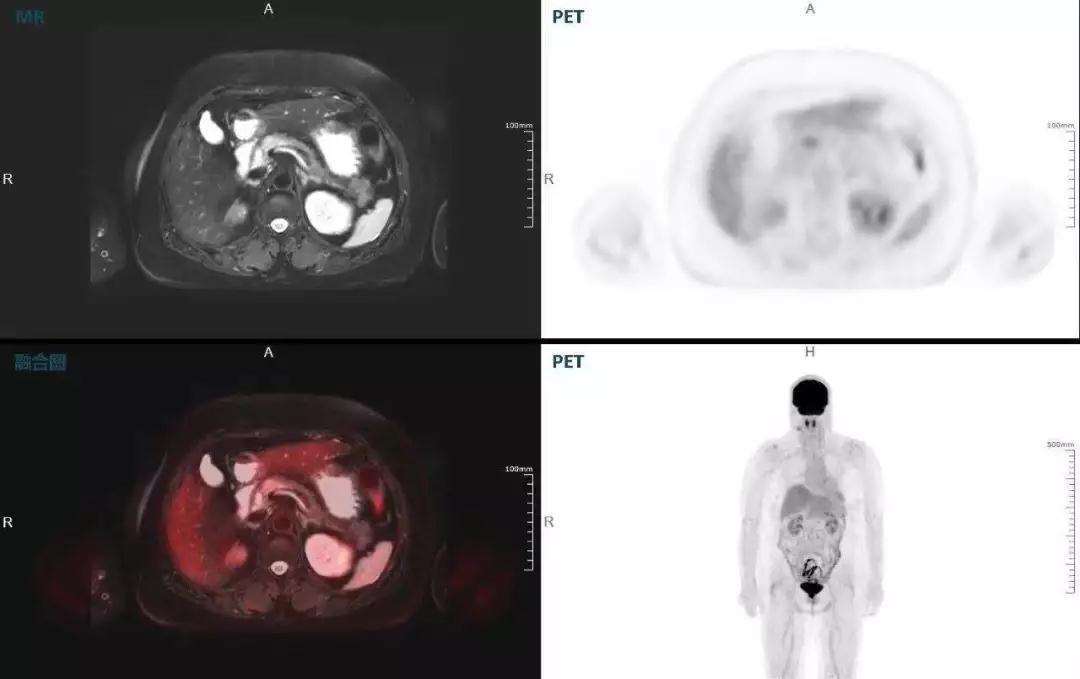

胰腺癌

中山醫(yī)院核醫(yī)學(xué)科在臨床實踐中發(fā)現(xiàn),基于聯(lián)影“時空一體”超清TOF PET/MR,不僅解剖信息和代謝信息能夠完美融合呈現(xiàn),同時精細(xì)展示局部病灶與周圍組織的復(fù)雜關(guān)系,并能全盤檢測病灶的全身轉(zhuǎn)移,為醫(yī)生臨床診斷提供更豐富信息。

(胰腺腫瘤,MR顯示胰腺體部信號異常,PET顯示稍高攝取,結(jié)構(gòu)改變和功能異常提示胰腺MT可能大。)